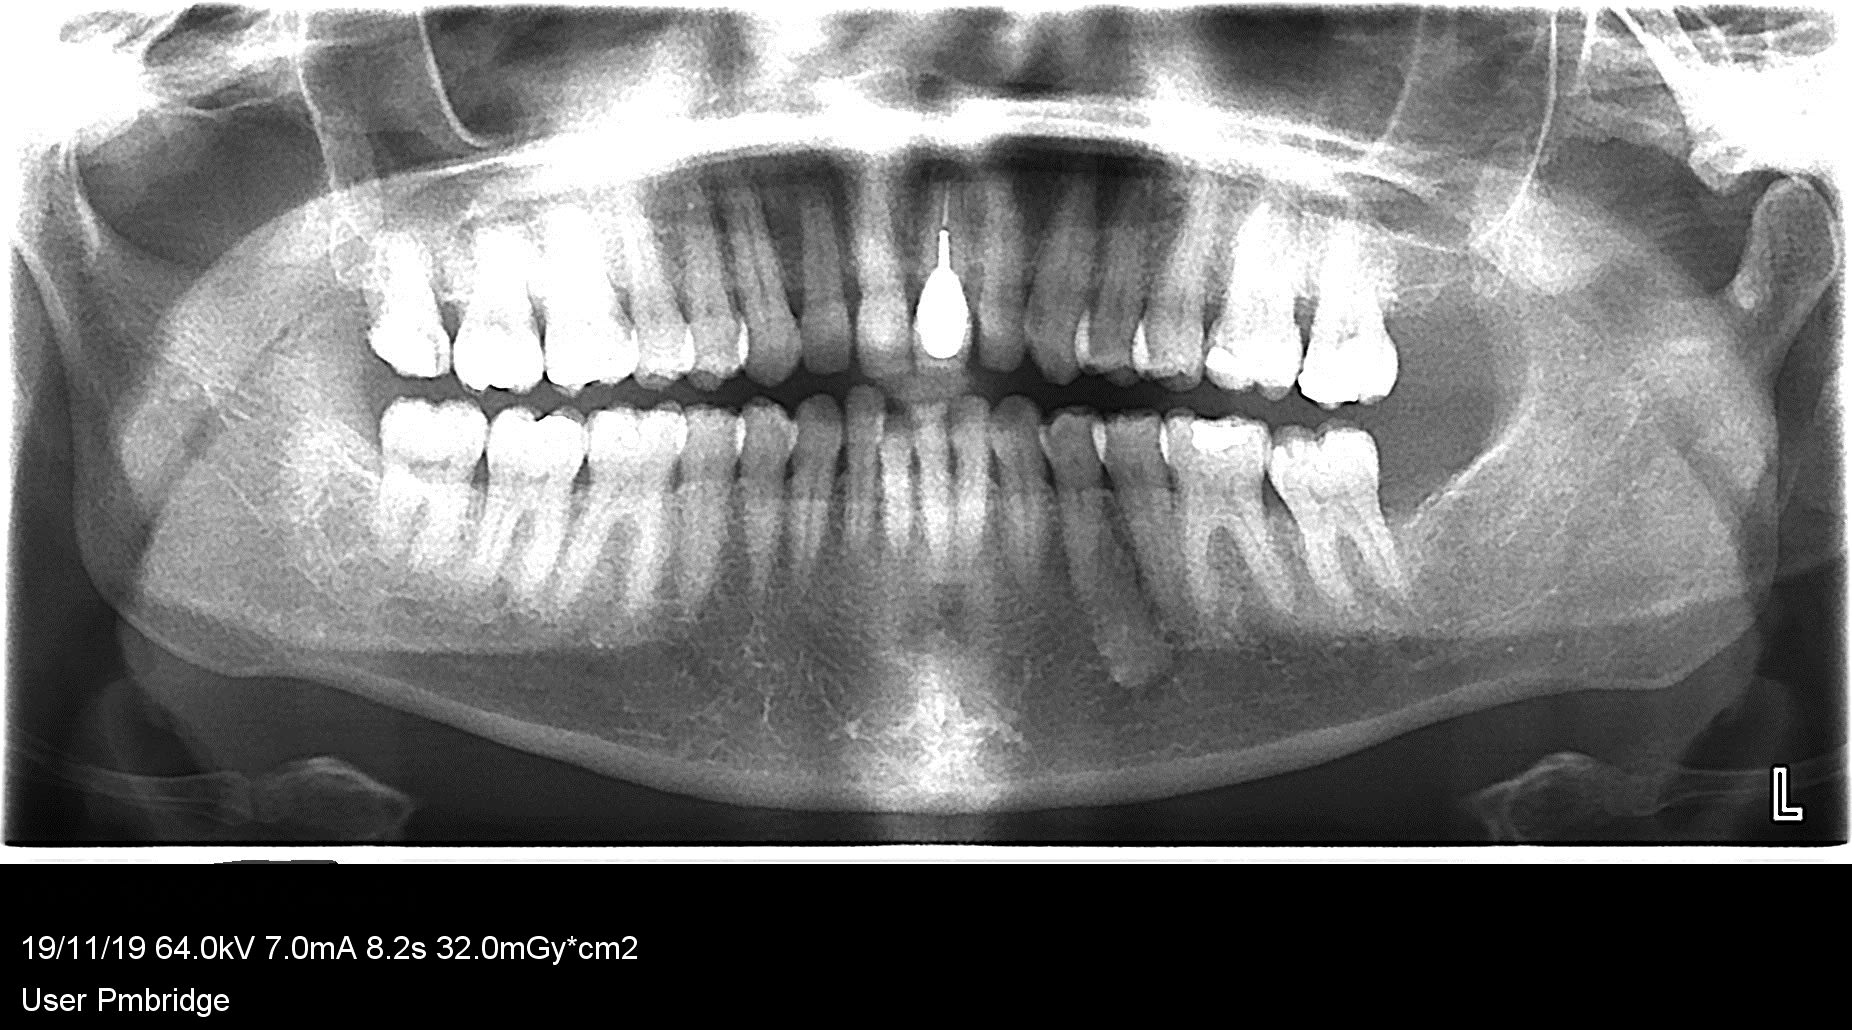

le diagnostic du radiologue après dentalscanner: il s'agit d'un ilôt condensant bénin. contours spiculés, venant focalement au contact de la corticale osseuse. vous feriez d'autres investigations?

entre 34/35

Aspect de cémentome, rien à faire